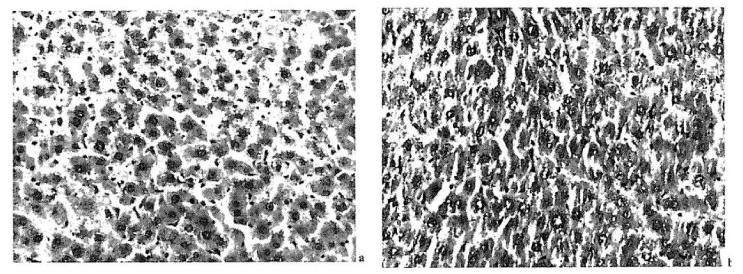

| Figure 6: Therapeutic influence of electron-transferred alkaloid injections on D-GalN traumatized livers. (a) The traumatization mimics the lesions caused by hepatitis B virus10, when lesions were inside the cells In (b) the cell architecture was regenerated after a complex procedure, which is still awaiting detailed studies. The sinusoids are opened and the blockages causing giant cell growth have disappeared. |